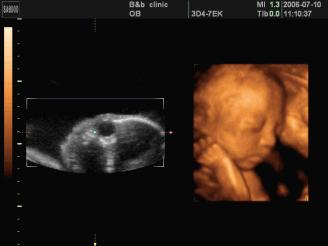

6、四维彩超:可能是土黄色,录像,动态,能够刻录成光盘,有排畸作用;

图片来源于百度图片